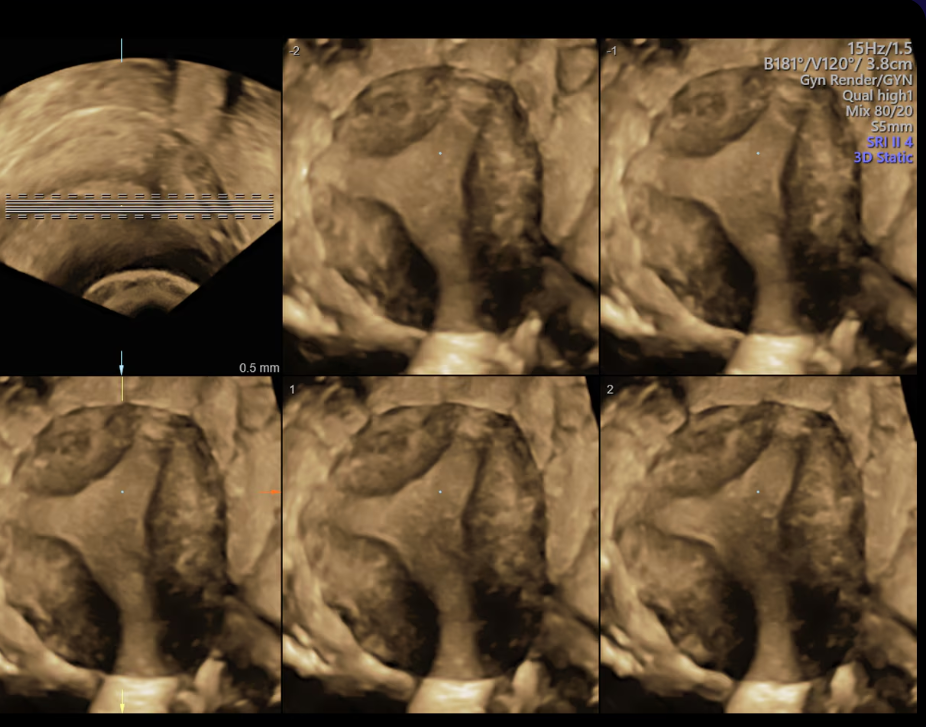

The S8 delivers excellent image clarity and penetration, highly sensitive color Doppler, and easy-to-use 3D/4D tools that help provide even more information.

Simplify 3D/4D acquisitions using SonoRenderlive – which automatically adjusts rendering placement during volume acquisition.

Helps simplify analysis and documentation of dynamic studies by simultaneously displaying views of multiple parallel slices of a volume data set.